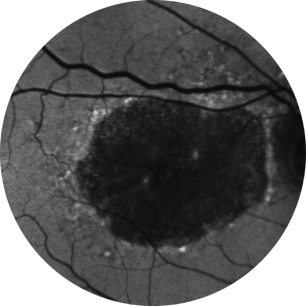

Avaliação inicial Ano 1

BCVA 20/63+, área de AG de 5,18 mm2

Avaliação inicial Ano 2

BCVA 20/80-2, área de AG de 10,39 mm2

Avaliação inicial Ano 5

BCVA 20/200, área de AG de 18,58 mm2

As imagens são cortesia do Dr. David Elchenbaum, da Retina Vitreous Associates of Florida.

BCVA = melhor acuidade visual corrigida (best corrected visual acuity).